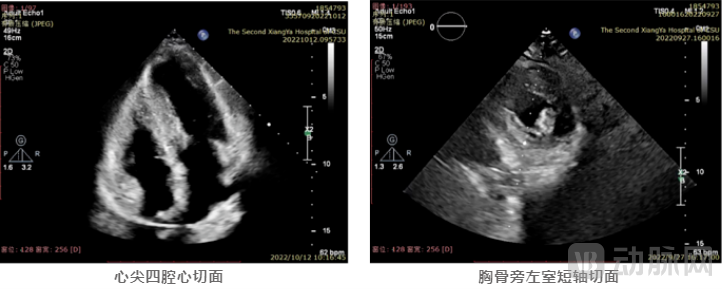

患者为65岁女性,1年前出现胸闷、气促加重、伴夜间阵发性呼吸困难等现象,药物治疗后症状仍未缓解。患者心脏彩超提示:LVEDD 42mm, LAD 36mm,EF 65%。室间隔非均匀性显著增厚,最厚处厚度22mm,左室后壁增厚为14mm,左室流出道梗阻(重度),见SAM征阳性。伴有二、三尖瓣轻度反流,主动脉瓣钙化并轻度反流。LVOT收缩期流速明显增快,约6.1m/s,PGmax高达150mmHg。

术前,技术团队利用三维重建技术,定制完全针对该患者疾病解剖特征的器械入路,精确识别肥厚区域。随后对其模拟消融路径,计划连续消融8个位点,术前预估各位点所需的消融能量范围和深度,确定了由前间隔至后间隔的消融策略。

术中,方臻飞教授熟练操控DragonFire,根据术前确定的消融策略,连续对前间隔、中间隔基底部最为肥厚的心肌区域进行了精准的定位、穿刺,并进行对应能量范围的消融。